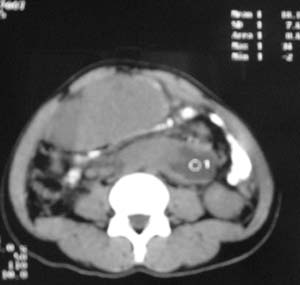

以下是引用zjzjr在2007-9-27 22:20:00的发言:[br]肠腔受推移,未见明显扩张及液平,所以考虑是肠外病灶, 间叶源性肿瘤?脂肪瘤?建议增强。

以下是引用guzhongliangddd在2007-9-27 23:21:00的发言:[br][br]与肠内高密度相同,病灶应该没有钙化,我认为首先考虑是间叶组织的良性肿瘤。建议楼主做后重建观察。中线区域大血管旁未见确切增大淋巴结。病灶对肠道只是推移关系。

以下是引用余辉在2007-9-27 22:24:00的发言:[br]暂考虑肠道间质来源肿瘤如小肠平滑肌肉瘤/瘤可能,应该增强